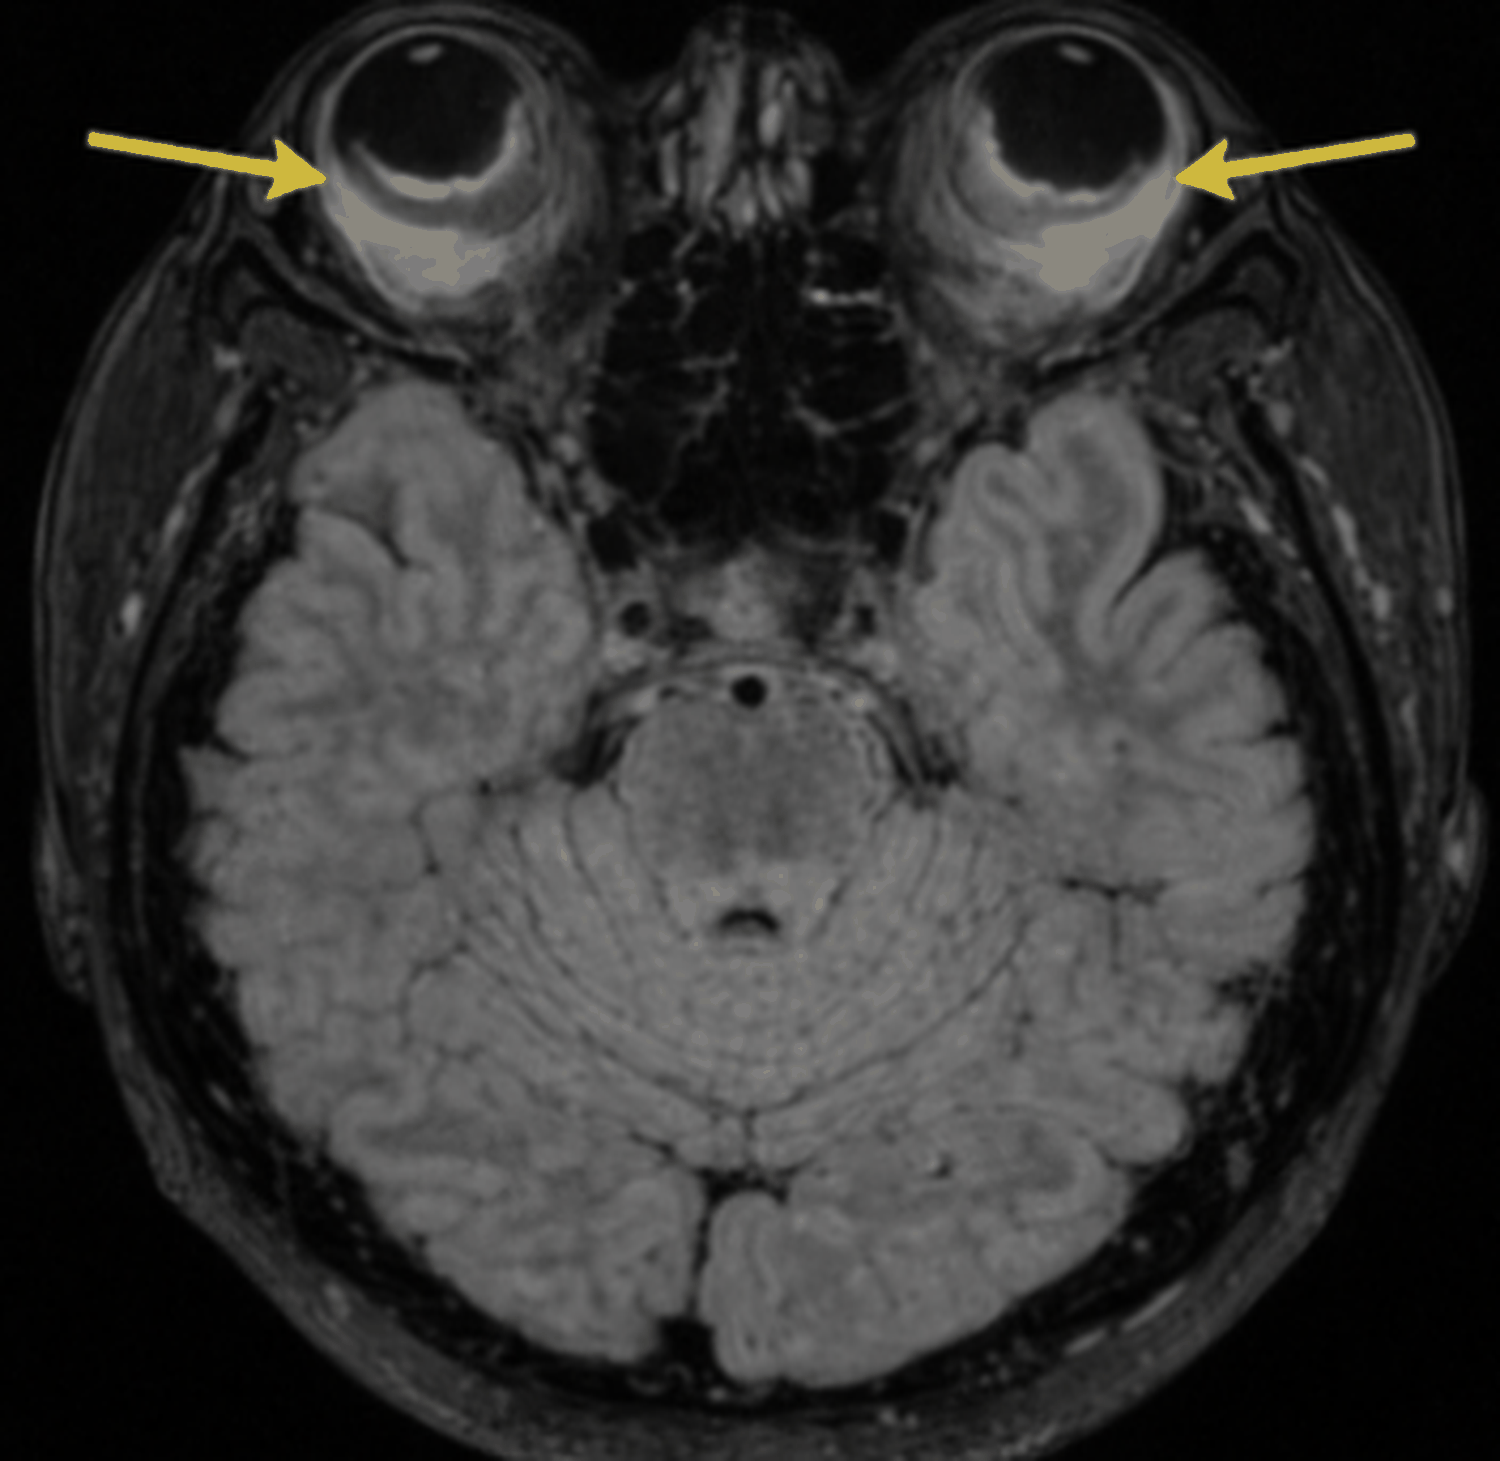

On postoperative day 2, the patient complaint of acute sudden loss of vision in one eye and blurring in contralateral eye despite of controlled blood pressure and reduced proteinuria (+1). Repeated lab results were in normal range. Urgent ophthalmology and neurology consultation were obtained. Fundoscopic examination revealed normal optic discs and red reflexes bilaterally with no papilledema. A CT scan of the brain was normal but MRI brain and orbits revealed bilateral serous retinal detachment (Figure 1).

Figure 1: MRI: showing bilateral serous retinal detachment.

The pathophysiology of serous retinal detachment in pre-eclampsia involves choroidal ischemia and breakdown of the blood-retinal barrier leading to fluid accumulation in the subretinal space without retinal tear [9,10]. This typically presents bilaterally, as in our case and is often associated with severe hypertension, proteinuria and other signs of end-organ dysfunction [1]. The patient’s MRI findings demonstrating bilateral serous retinal detachment without underlying retinal breaks are consistent with this mechanism.